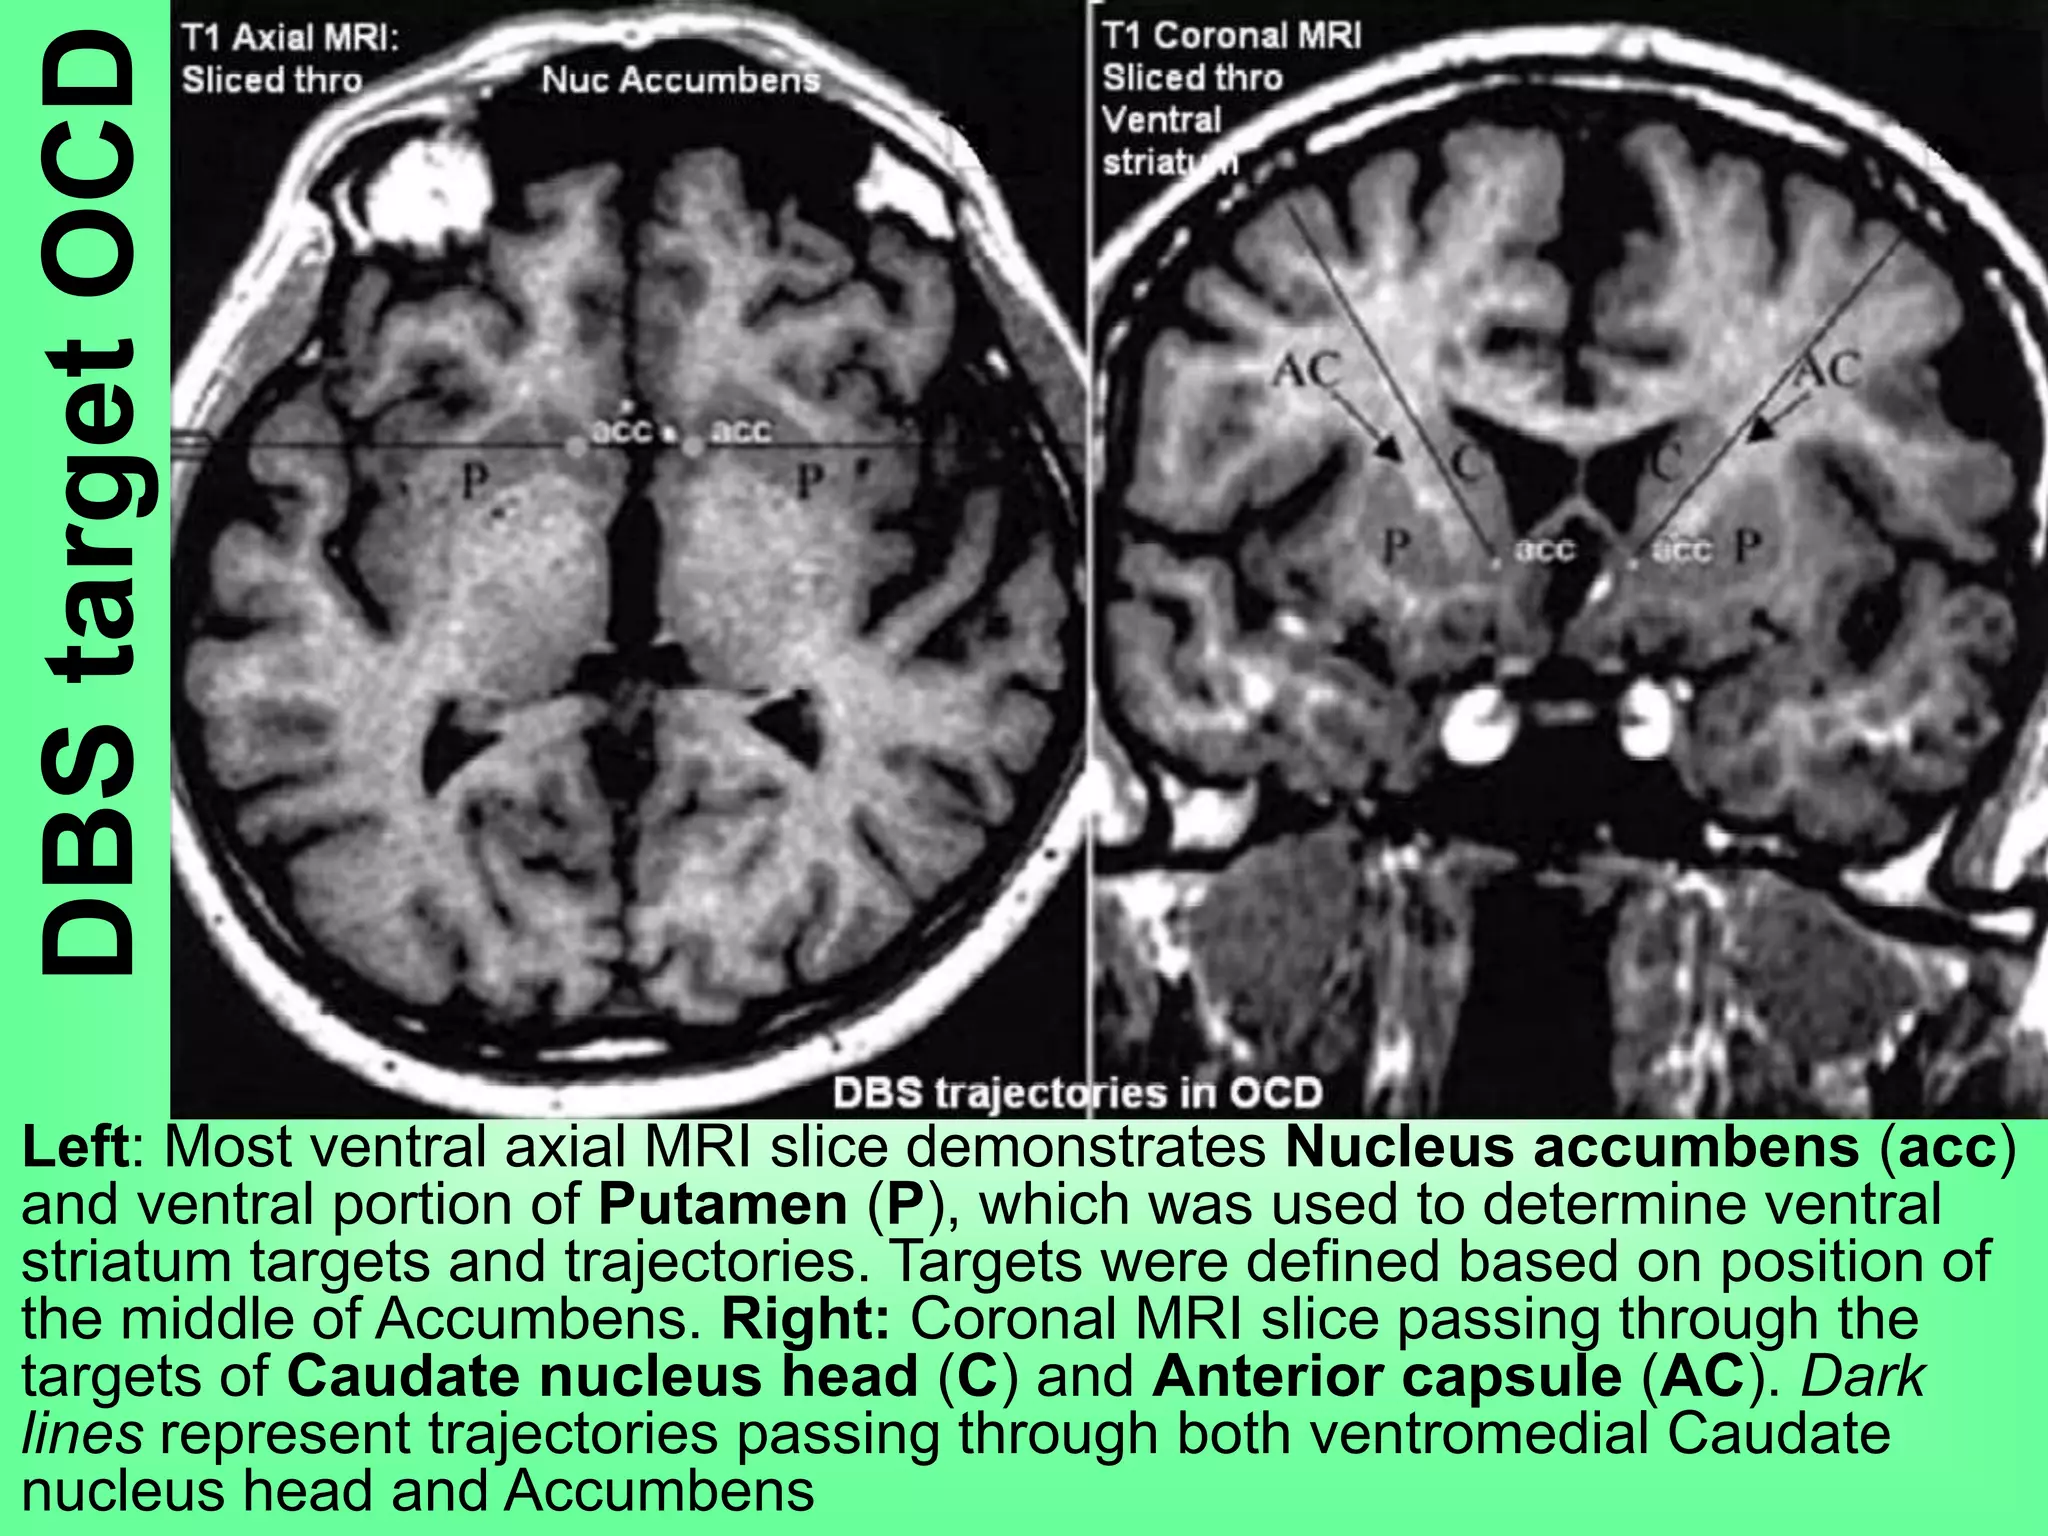

Left: Most ventral axial MRI slice demonstrates Nucleus accumbens (acc)

and ventral portion of Putamen (P), which was used to determine ventral

striatum targets and trajectories. Targets were defined based on position of

the middle of Accumbens. Right: Coronal MRI slice passing through the

targets of Caudate nucleus head (C) and Anterior capsule (AC). Dark

lines represent trajectories passing through both ventromedial Caudate

nucleus head and Accumbens

DBStargetOCD Left: Most ventralaxial MRI slice demonstrates Nucleus accumbens (acc) and ventral portion of Putamen (P), which was used to determine ventral striatum targets and trajectories. Targets were defined based on position of the middle of Accumbens. Right: Coronal MRI slice passing through the targets of Caudate nucleus head (C) and Anterior capsule (AC). Dark lines represent trajectories passing through both ventromedial Caudate nucleus head and Accumbens